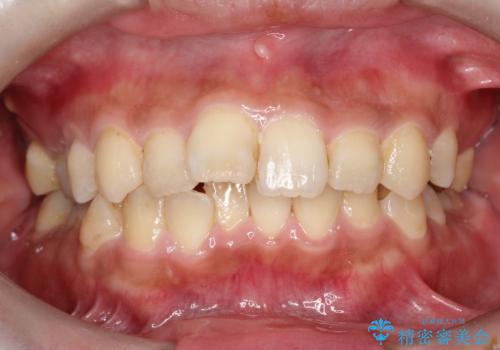

- 主訴:学生時代に矯正治療したが、後戻りしてしまった。上下前がのガタつきを治したい。

食品関係に努めており、頻繁に物を口にするためマウスピース矯正は装着時間を守ることが難しいことから非抜歯のワイヤー装置にて治療することとなりました。